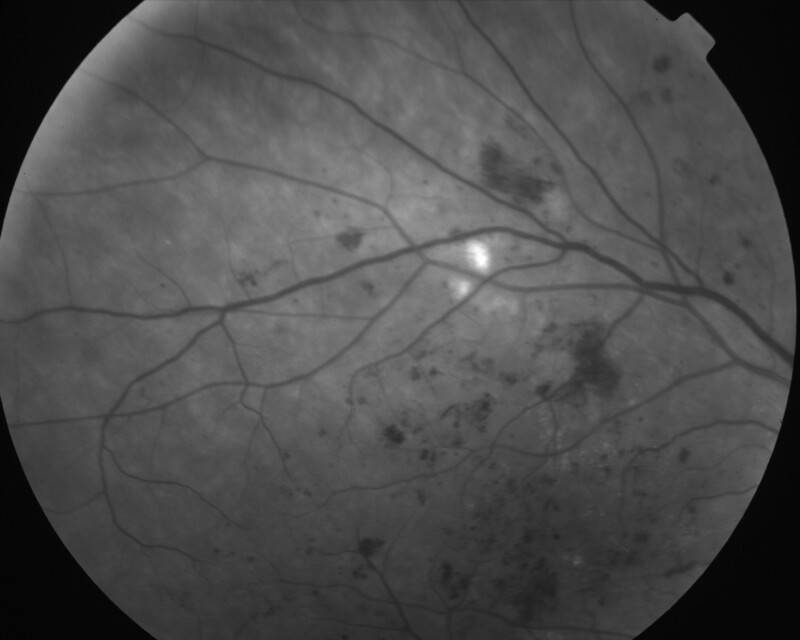

RETINOPATHIE DIABETIQUE NON PROLIFERANTE SEVERE

IMG0002.JPG